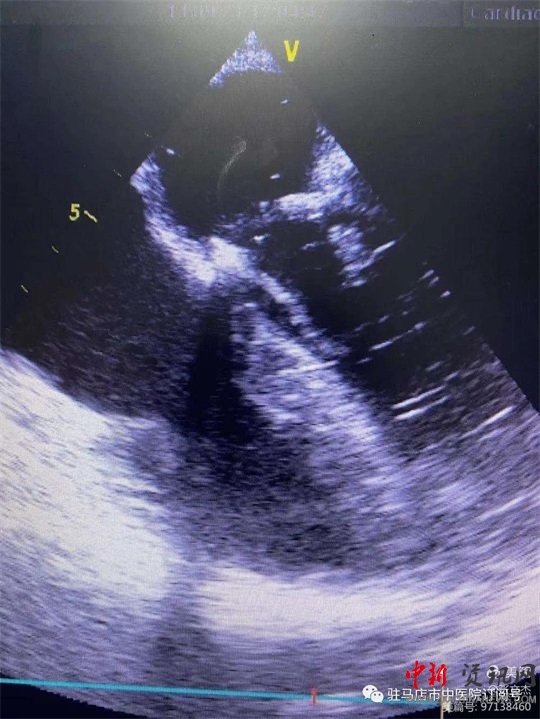

復(fù)跳后經(jīng)食道心臟超聲,二尖瓣功能較術(shù)前明顯改善。